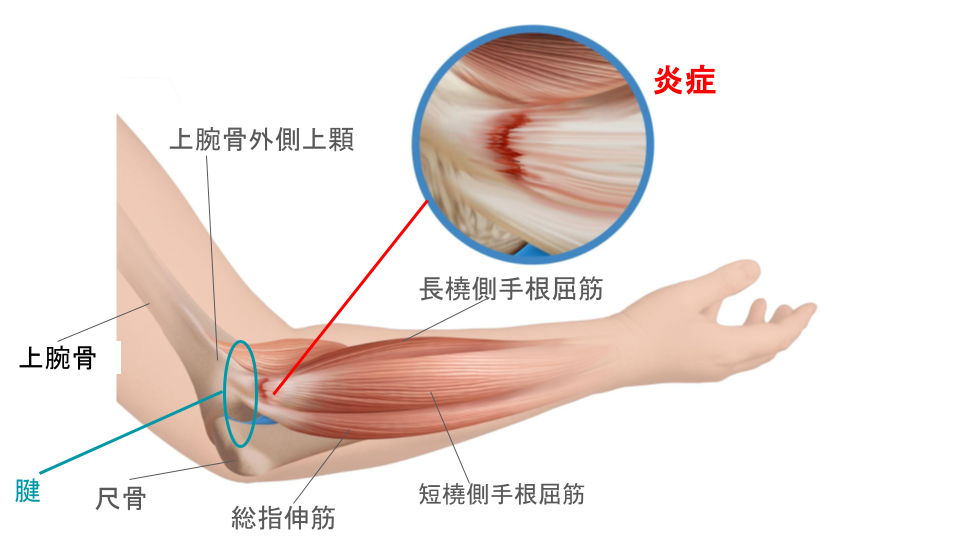

日常生活の何気ない動作で、肘の外側に痛みを感じる場合、その原因として最も多いのが「上腕骨外側上顆炎(じょうわんこつがいそくじょうかえん)」と呼ばれる状態です。

「上腕骨外側上顆炎」の言葉は聞き慣れないかもしれませんが、一般的には「テニス肘」と呼ばれています。

肘の外側には、手首や指を動かすための筋肉や腱が集まっており、これらの筋肉や腱は、肘の外側の骨の出っ張り(上腕骨外側上顆)に付着しています。

手首や指を繰り返し使う動作をすることで、これらの筋肉や腱に負担がかかり、小さな傷ができて炎症や痛みを起こします。

上記の動作に共通するのは「手首を反らす動き」や「肘に負担のかかる姿勢」です。これらの動きを繰り返すことで、肘の外側の筋肉や腱が引っ張られ、炎症が起こりやすくなります。